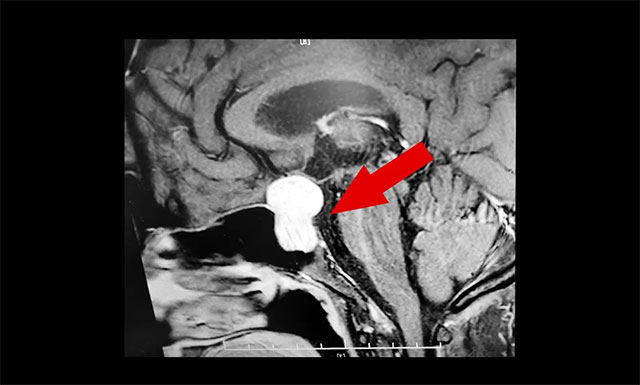

随后,患者进行了头部鞍区MRI平扫+增强,结果显示:蝶鞍显著扩大,鞍区见一典型的“8字”状肿物,大小约2.2×1.8×2.7cm,病变像鞍上生长,占据鞍上池,推移视交叉;向下生长,鞍底骨质受压变薄;向鞍旁生长,侵及海绵窦、局部包裹约1/3。

▲ 术前MR影像:肿瘤向鞍内、鞍上、鞍旁发展,呈“哑铃形”

潘仁龙主任指出,垂体肿瘤向鞍上生长,占据鞍上池,压迫到视神经传导物,使患者视物出现异常。一般1-3cm的大腺瘤或大于3cm的巨大腺瘤,都会引起不同程度的视力问题。

李士其教授、潘仁龙主任、吴治群博士会诊后指出:肿瘤主体位于鞍内、鞍上、鞍旁发展,呈“哑铃”形。从影像学资料上看,发现瘤体已经非常大了,属于垂体大腺瘤。瘤体占据鞍区,并向蝶窦和鞍上发展,侵袭海绵窦,视神经、视交叉受压,所以需要马上进行手术切除,解除压迫。若任其发展,将来有失明的风险。